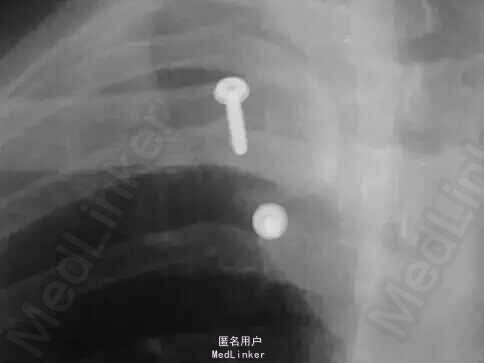

查体:胸前部略肿胀,左侧胸锁关节处隆起,触痛,可触及浮动感,左肩活动时疼痛加重,余未见异常。 辅检:门诊X线片:左侧胸锁关节脱位

诊断:左侧胸锁关节脱位 治疗:行切开复位内固定术,应用两枚螺钉及不可吸收线八字固定